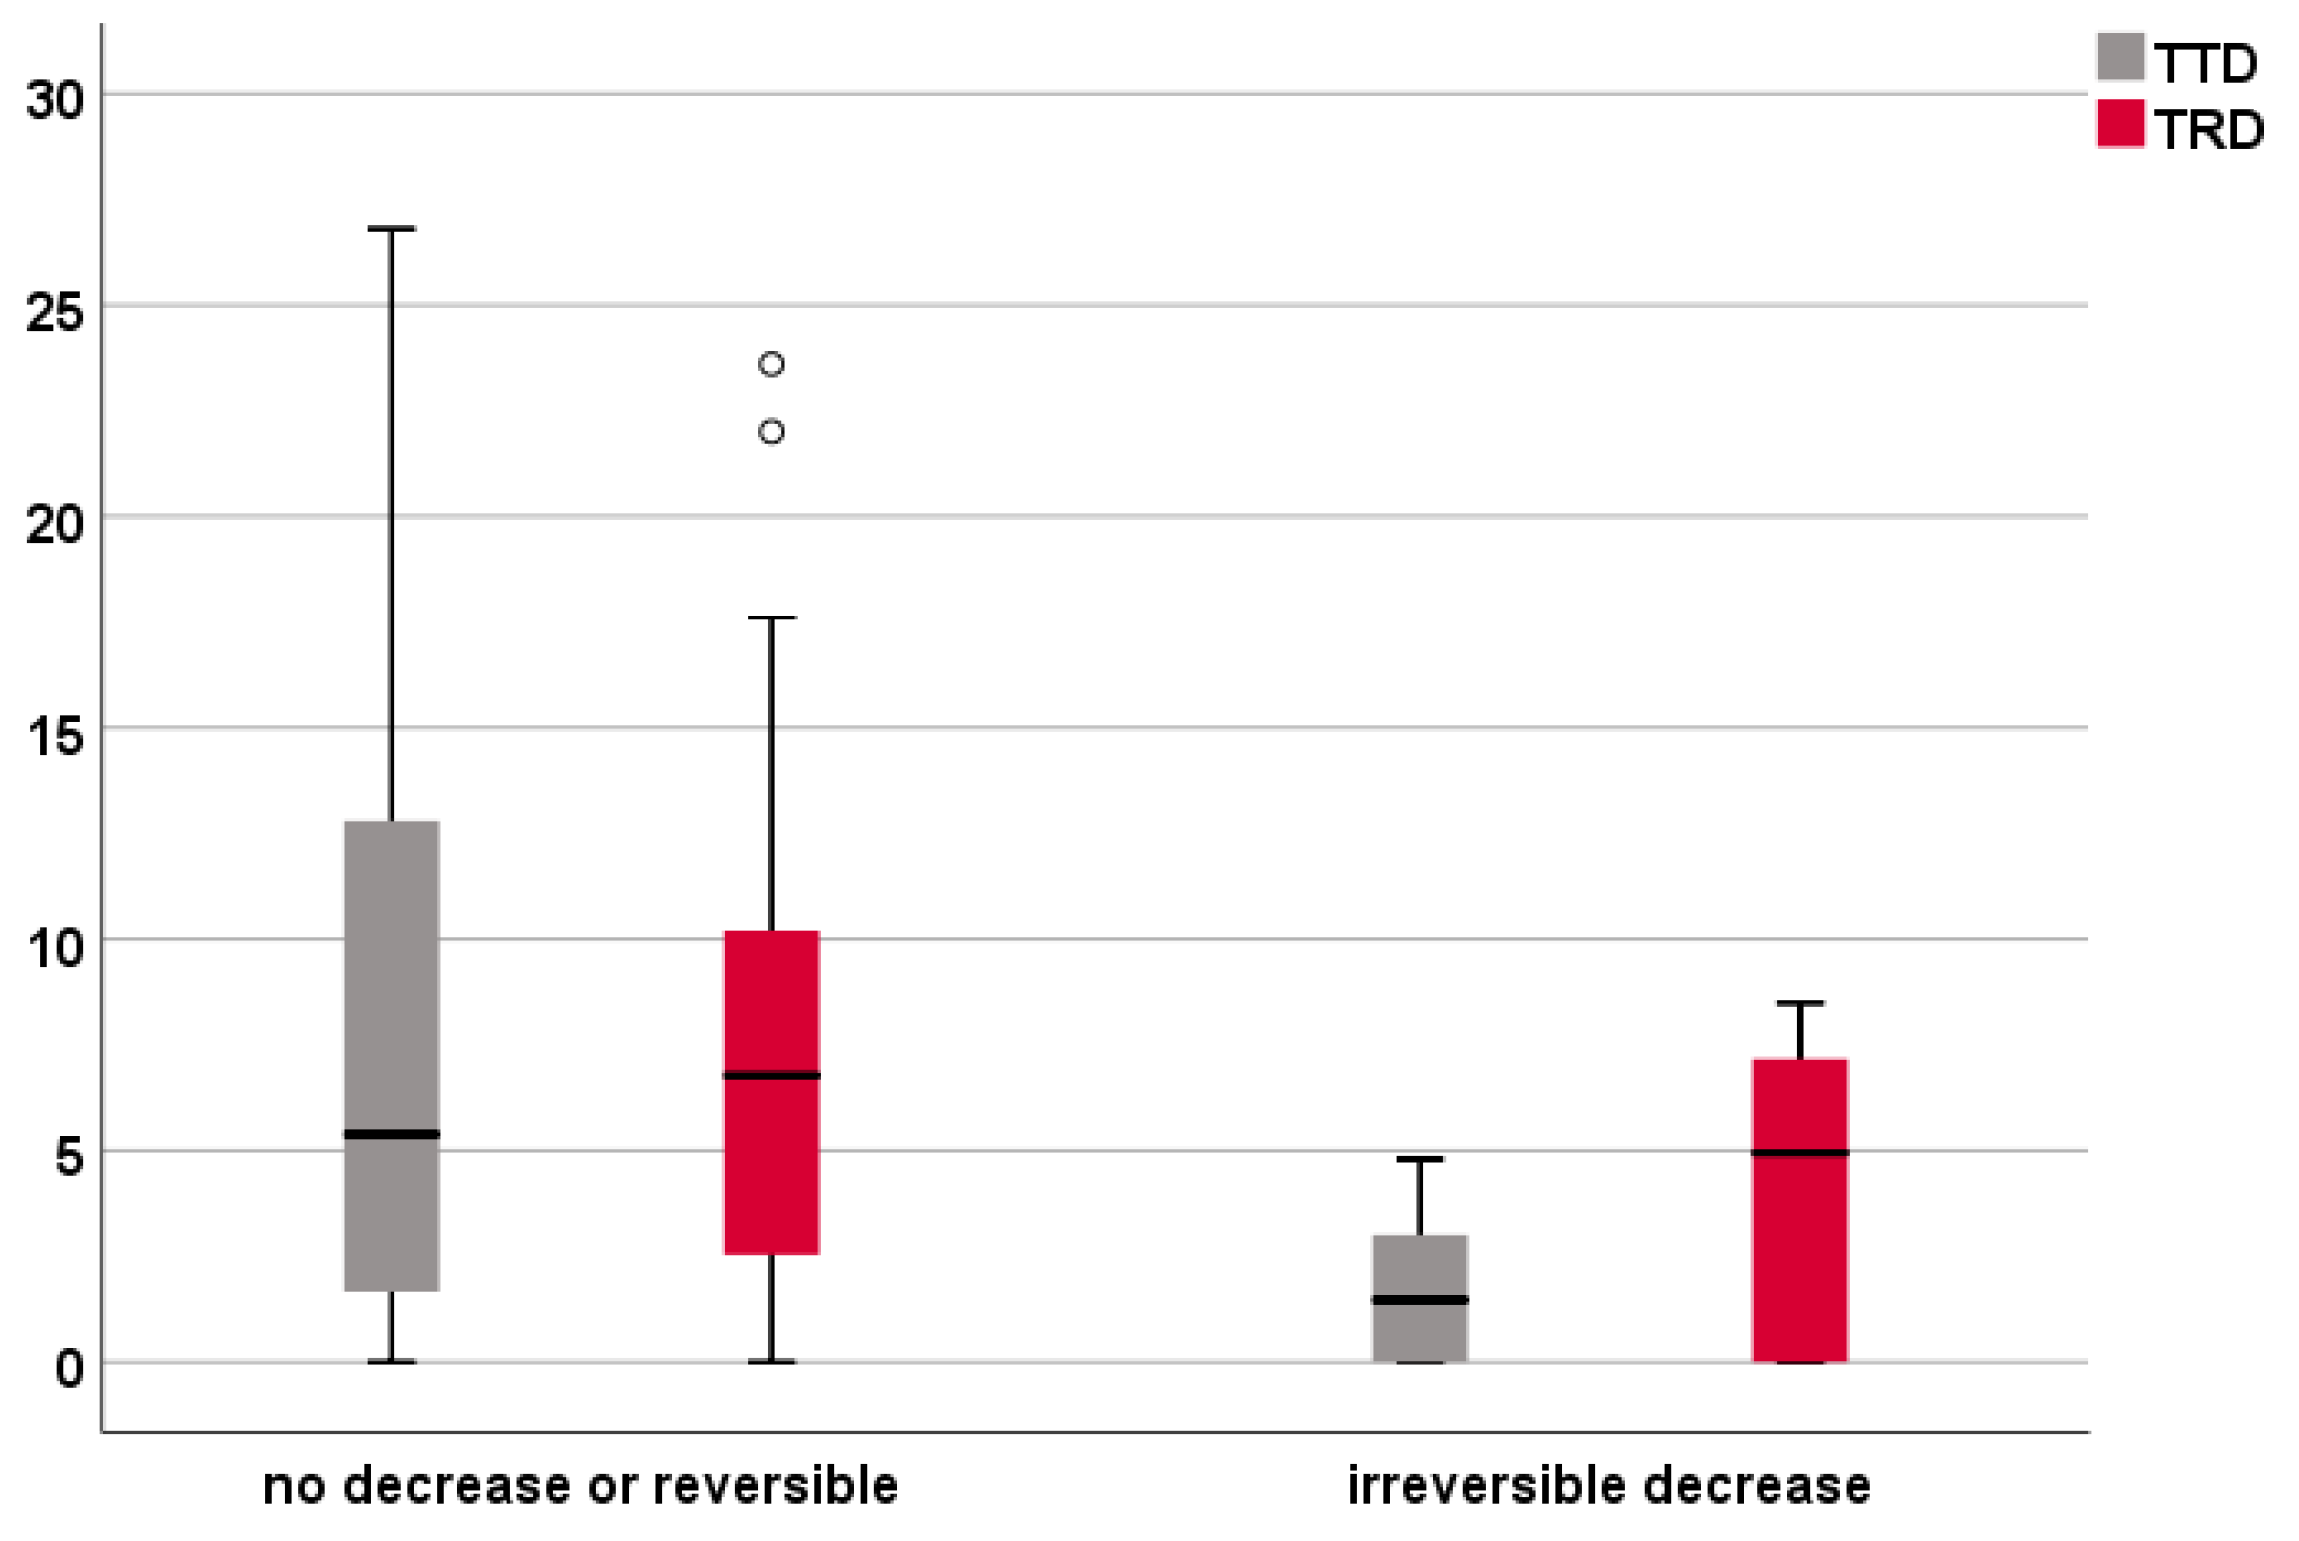

3.5. Analysis of the IOM Subgroup

| Cases with No Decrease or Reversible (n = 42) | Cases with Irreversible Decrease (n = 6) | P (Mann–Whitney U Test) | ||

|---|---|---|---|---|

| TTD | intersection | 9 | 3 | |

| 0–8 mm | 16 | 3 | ||

| >8 mm | 17 | 0 | ||

| median (IQR) | 5.4 (1.6–12.8) mm | 1.5 (0–3.5) mm | 0.033 | |

| TRD | intersection | 5 | 2 | |

| 0–8 mm | 20 | 3 | ||

| >8 mm | 17 | 1 | ||

| median (IQR) | 6.8 (1.4–10.6) mm | 4.9 (0–7.5) mm | 0.249 |